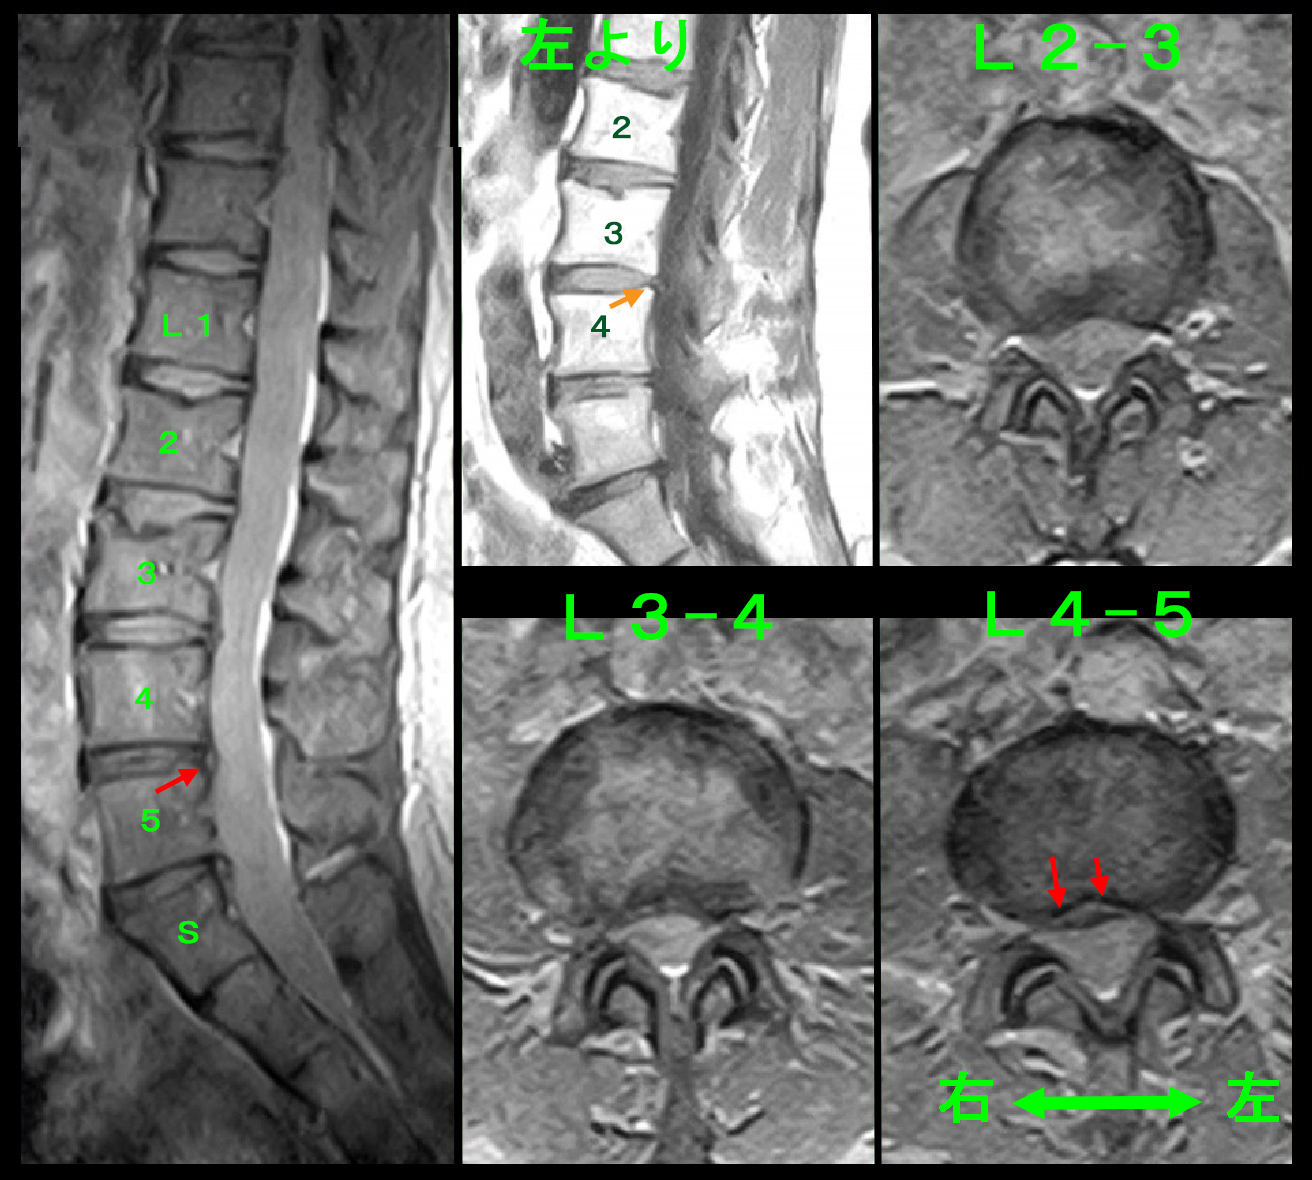

腰椎MRI検査でも目立った所見は確認されませんが、L23・L34・L45・L5Sの各椎間板に軽度の椎間板ヘルニアが確認されました。どこの椎間板が明確に脊髄を圧迫していて、それが坐骨神経痛の原因であろうと推察できません。しかし、医師は原因を見つけ出さなければなりません。そのような場合、私は4分割の左上のT1矢状断の画像のオレンジ矢印で示すL34の椎間板の突出が他の椎間板に比して白っぽくなっていると評価しました。私はT1の椎間板の突出部位が白い場合、そこが最近悪化した箇所であると判断しているので、Yさんの病因はL34の椎間板ヘルニアであろうと判断し、左L4神経根ブロックを施行しました。

Yさんの痛みの原因はL34ではありませんでした。ならばどの椎間板なのかをMRI所見からみつけださなければなりません。するとT1の矢状断でL5Sの左側で他の椎間板高位より突出が認められ(オレンジ矢印)、4分割の下の2つの画像では左側で軽度の脊髄圧迫、右側では脊髄の外側に中等度のヘルニアがあるようにもみれると評価し、これが病因であろうと判断しました。左S1神経根ブロックを行い、1週間後に再診予定としました。

元々MRI画像の水平断ではL45での脊髄は逆三角形となっていて、最も脊髄の圧迫の強い高位だったのですが、椎間板ヘルニアは右側で優位であるため、左坐骨神経痛を訴えるYさんの病因ではないであろうと除外していました(赤矢印)。でもYさんの病因はL34でもL5Sでもありませんでした。L23の水平断の圧迫はごく軽微ですし、これも右優位です。L34でもL5Sでもなければ、L45しかないと判断しました。同日、右L5神経根ブロックを施行しました。